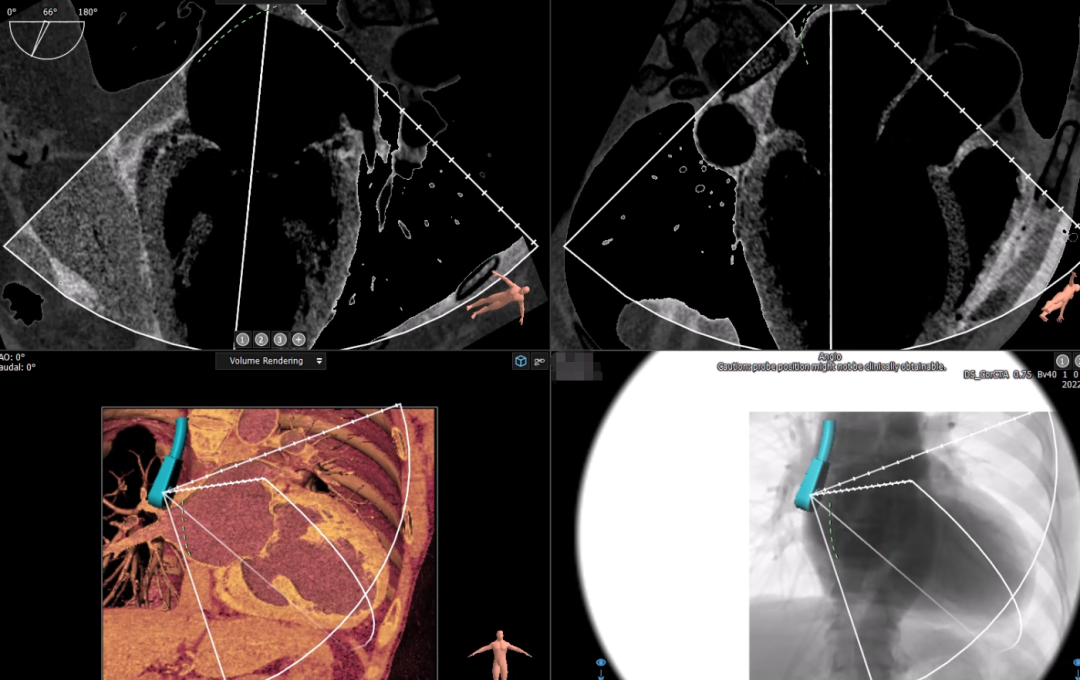

经过瑞金医院心外科MDT团队综合讨论评估该患者病情后,患者为重度FMR患者,为传统外科手术极高危患者,决定进行MitraFix®经心尖二尖瓣植入。术前心脏CTA瓣环面积折算最大直径41.5 mm 模拟植入34号二尖瓣瓣膜, 心室Neo LVOT面积可。

术前心尖入路评估